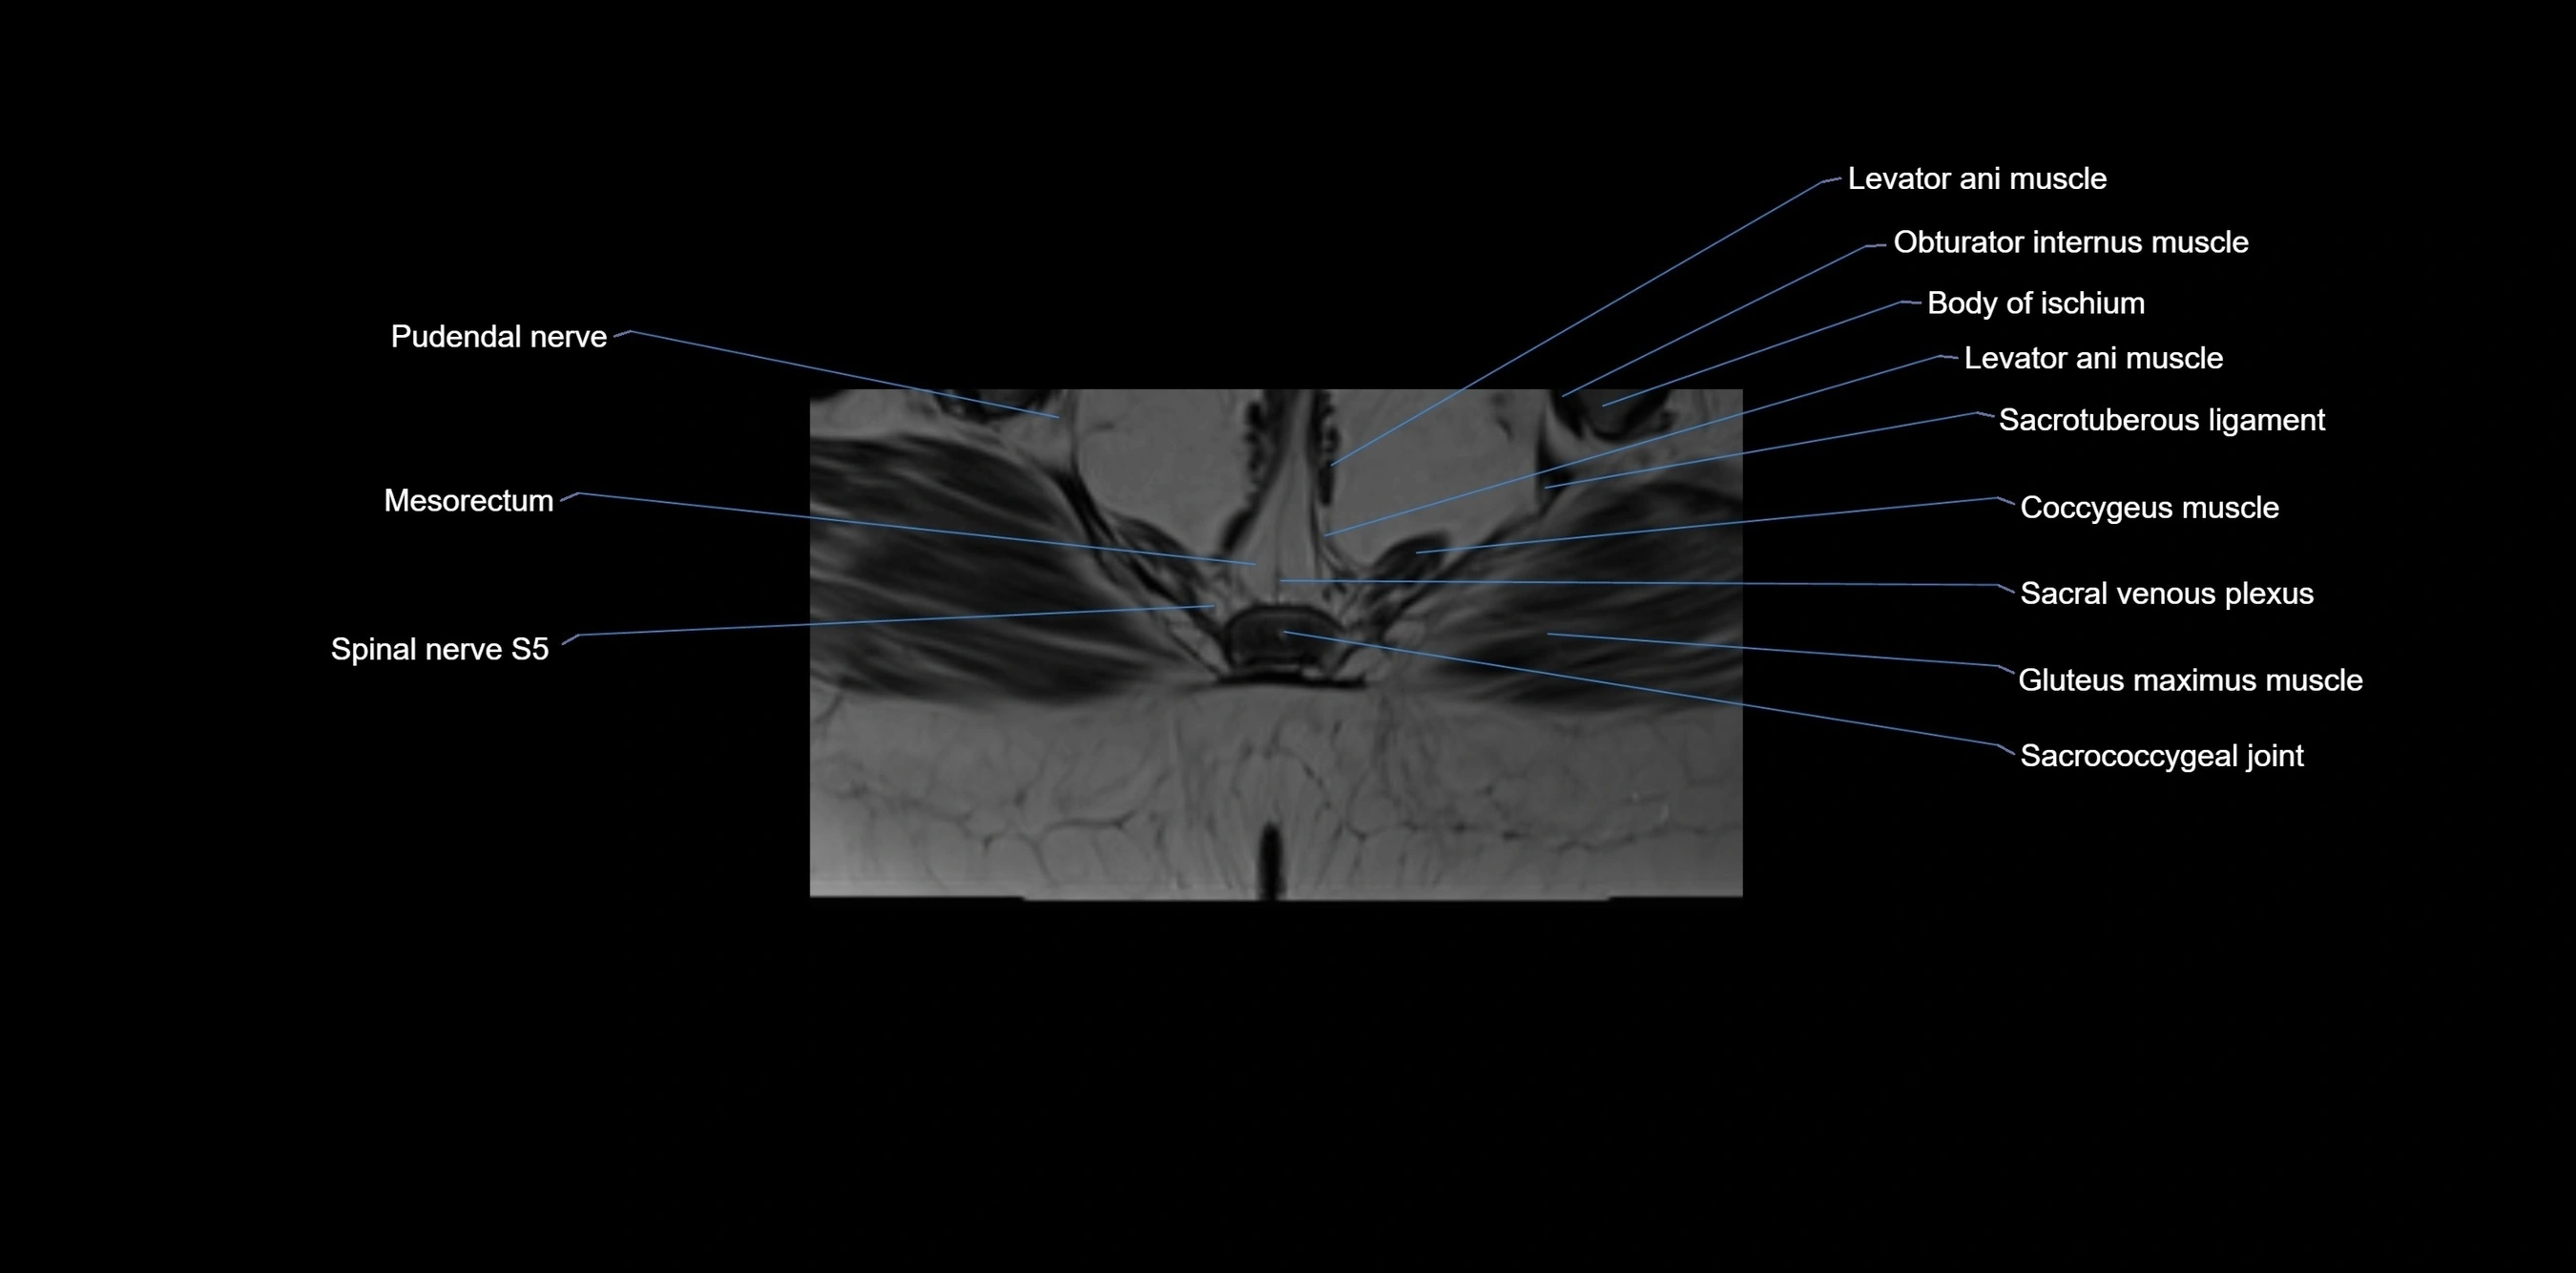

CT image

image